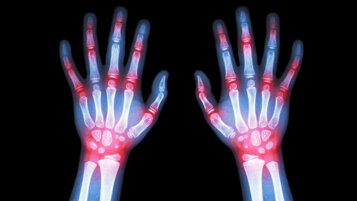

Artrite reumatoide

La più nota delle malattie articolari infiammatorie croniche, è una poliartrite simmetrica che colpisce soprattutto mani, polsi, piedi e ginocchia. Può esordire nelle prime decadi di vita, ma anche in età più avanzata.

Oltre al coinvolgimento articolare, la malattia può avere anche manifestazioni sistemiche, richiede quindi un inquadramento generale che consideri il Paziente nella sua globalità. La terapia è basata principalmente su farmaci di fondo ad azione immunosoppressiva.